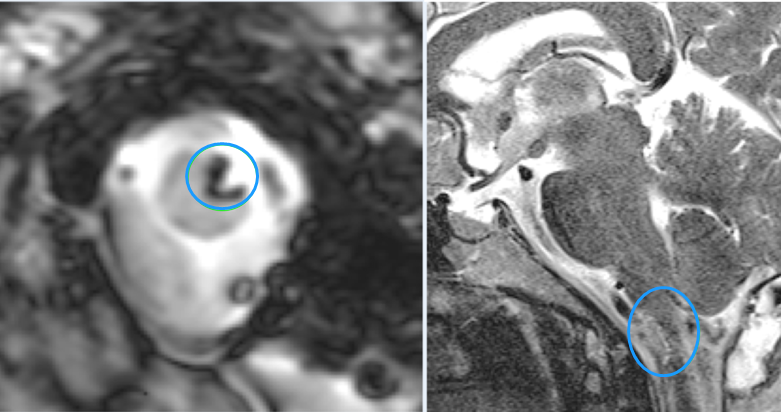

術(shù)前MR:高位頸髓-腦干延髓腦橋海綿狀血管瘤

診斷:高位頸髓-腦干延髓海綿狀血管瘤

手術(shù)過(guò)程:半坐位,遠(yuǎn)外側(cè)入路顯微鏡下全切腫瘤,骨瓣開(kāi)顱至腫瘤全切歷時(shí)約3小時(shí),手術(shù)順利。